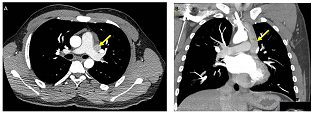

Torasik embriyonik venoz sistemin nadir bir anomaliyası: Sağ superior vena kavanın olmadığı persistan sol superior vena kava Dərc edilib: Cild 7, Nömrə 1, 2015 / Nəşr tarixi: 20.07.2015

S.Ə. Səmədli, V.P. Vəliyev, A. Asaliyeva, V.V. Həsənov